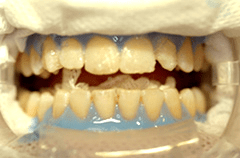

Abb. rechts Aufgesetzte Schutzbrille und UV-Schutz der Haut. Die Zähne werden in einer Sitzung 2-3mal gebleicht. Das Gel wird mit der Zoom® Metall-Halogenidlampe ohne Wärmewirkung auf die Zähne aktiviert.

Die Gingiva wird nach Isolierung des Arbeitsfeldes mit einem speziellen Schutzgel abgedeckt, um die Schleimhaut zu schonen. Um das optimale Ergebnis nach Auftragen des Bleichgels zu erhalten, empfiehlt sich die Verwendung einer speziellen Bleichlampe. Sie sollte ein exakt justierbares und genügend großes Belichtungsfenster besitzen, um ein gleichmäßig intensives Aufhellen der oberen und unteren Zahnreihe zu ermöglichen (wie z.B. die Metall-Halogenidlampe der Firma Discus Dental). Sollte während des Bleichvorganges trotz Schutz des Zahnfleisches und freiliegender Zahnhälse ein blitzartiges Ziehen an einem Zahn mit Füllung auftreten, ist das ein sicherer Hinweis dafür, dass die Füllung einen eventuell röntgenologischen nicht sichtbaren Randspalt aufweist. Füllungen sollten daher generell vor einem Bleaching abgedichtet werden. Die definitive Versorgung durch Schmelz-/Dentinadhäsion sollte etwa zehn Tage nach dem Bleichen durchgeführt werden, da dann der Zahn wieder komplett remineralisiert ist und daher wieder eine optimale adhäsive Verankerung und auch passende Farbauswahl möglich ist. Die bei uns im Hause zahlreich durchgeführten In-Office-Bleaching Sitzungen mit dem ZOOM® Zahnnaufhellungssystem führten in keinem Fall zu deutlicher Postsensibilität der Zähne, und kann daher aus meiner Sicht uneingeschränkt für das schnelle, wirkungsvolle und dennoch schonende In-Office-Bleaching  empfohlen werden.